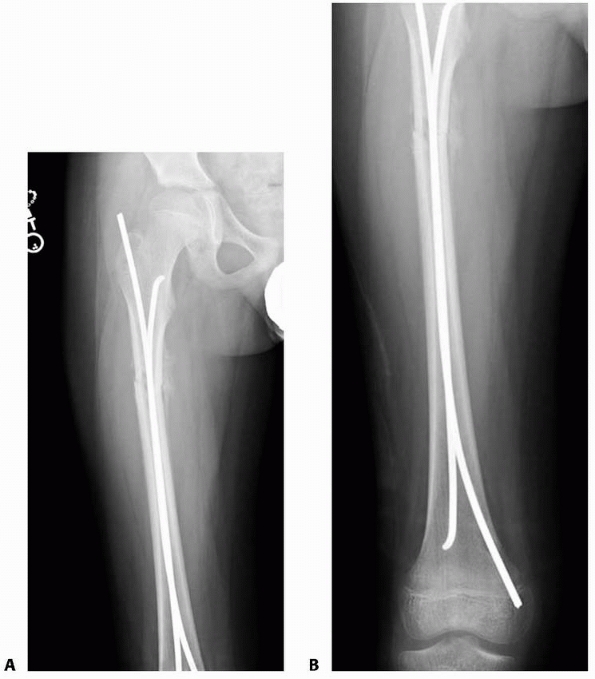

fractures, a dominant technique in Europe since the 1970s, has been

rapidly adopted throughout North America as the most popular method of

fixation for midshaft femoral fractures in children between the ages of

5 and 11 years. The flexible intramedullary nailing technique can be

done with either stainless steel nails169 or titanium elastic nails.

most centers throughout the world has been retrograde, with small

medial and lateral incisions just above the distal femoral physis;

however, some prefer an antegrade technique, with entry in the

subtrochanteric area. The primary advantages of a proximal insertion

site are a fewer knee symptoms postoperatively. Bourdela22

compared retrograde and antegrade (ascending and descending) flexible

intramedullary rodding in a group of 73 femoral fractures. Sixty one

fractures were treated with antegrade nails and 12 with retrograde

nails. All children with antegrade nailing had good clinical and x-ray

results; all 12 children with retrograde nails had knee pain that

impaired knee motion until the nails were removed. An antegrade

transtrochanteric approach was recommended by Carey and Galpin,32

who reported excellent results in 25 patients without growth arrest of

the upper femur and no osteonecrosis. Satisfactory alignment and

fracture healing were obtained in all patients.